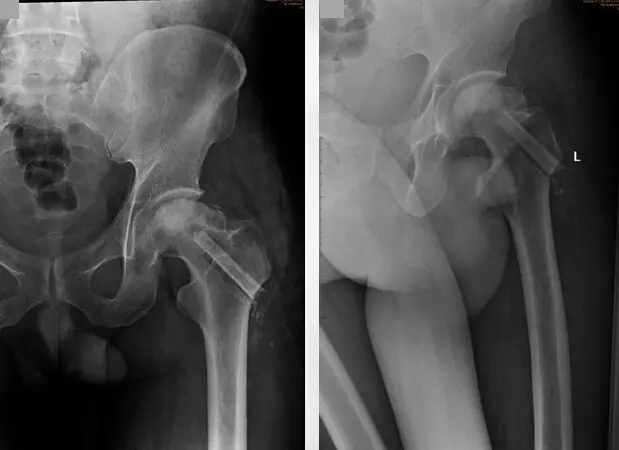

第二次术后复查X线